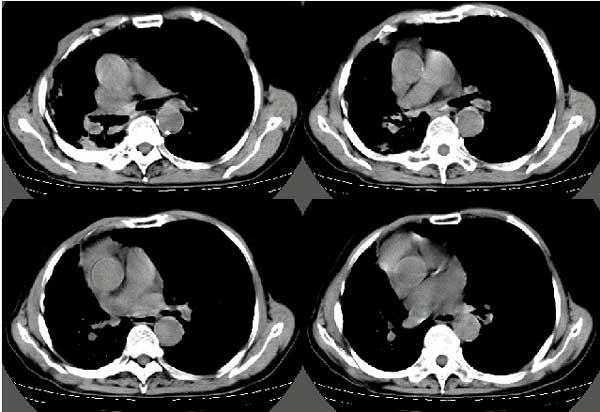

以下是引用扬仪在2005-5-12 20:46:40的发言:[br]右肺呈术后改变;双侧肺野散在分布斑片状、点状高密度病灶,(似可见“树芽征”);左上尖后段见斑团状高密度病灶(2个层面?),边缘毛糙,段性分布,与斜裂相邻,临近胸膜粘连;增强示病灶边缘强化,内呈水样密度;心影、纵隔右移,内可见4r淋巴结肿大。[br]意见:1、双肺继发性肺结核,左上为干酪病灶;[br] 2、矽肺合并感染;[br] 3、建议抗痨+抗炎。 [br]愚人之见,请高人指教!